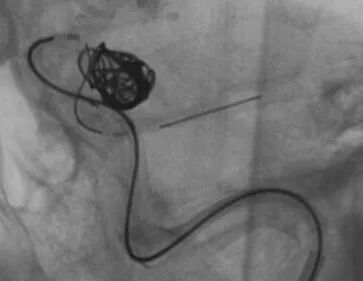

释放支架

找到支架与弹簧圈之间的切线位,继续填塞。支架很好地保护住了颈内动脉和后交通动脉

最后的填塞结果